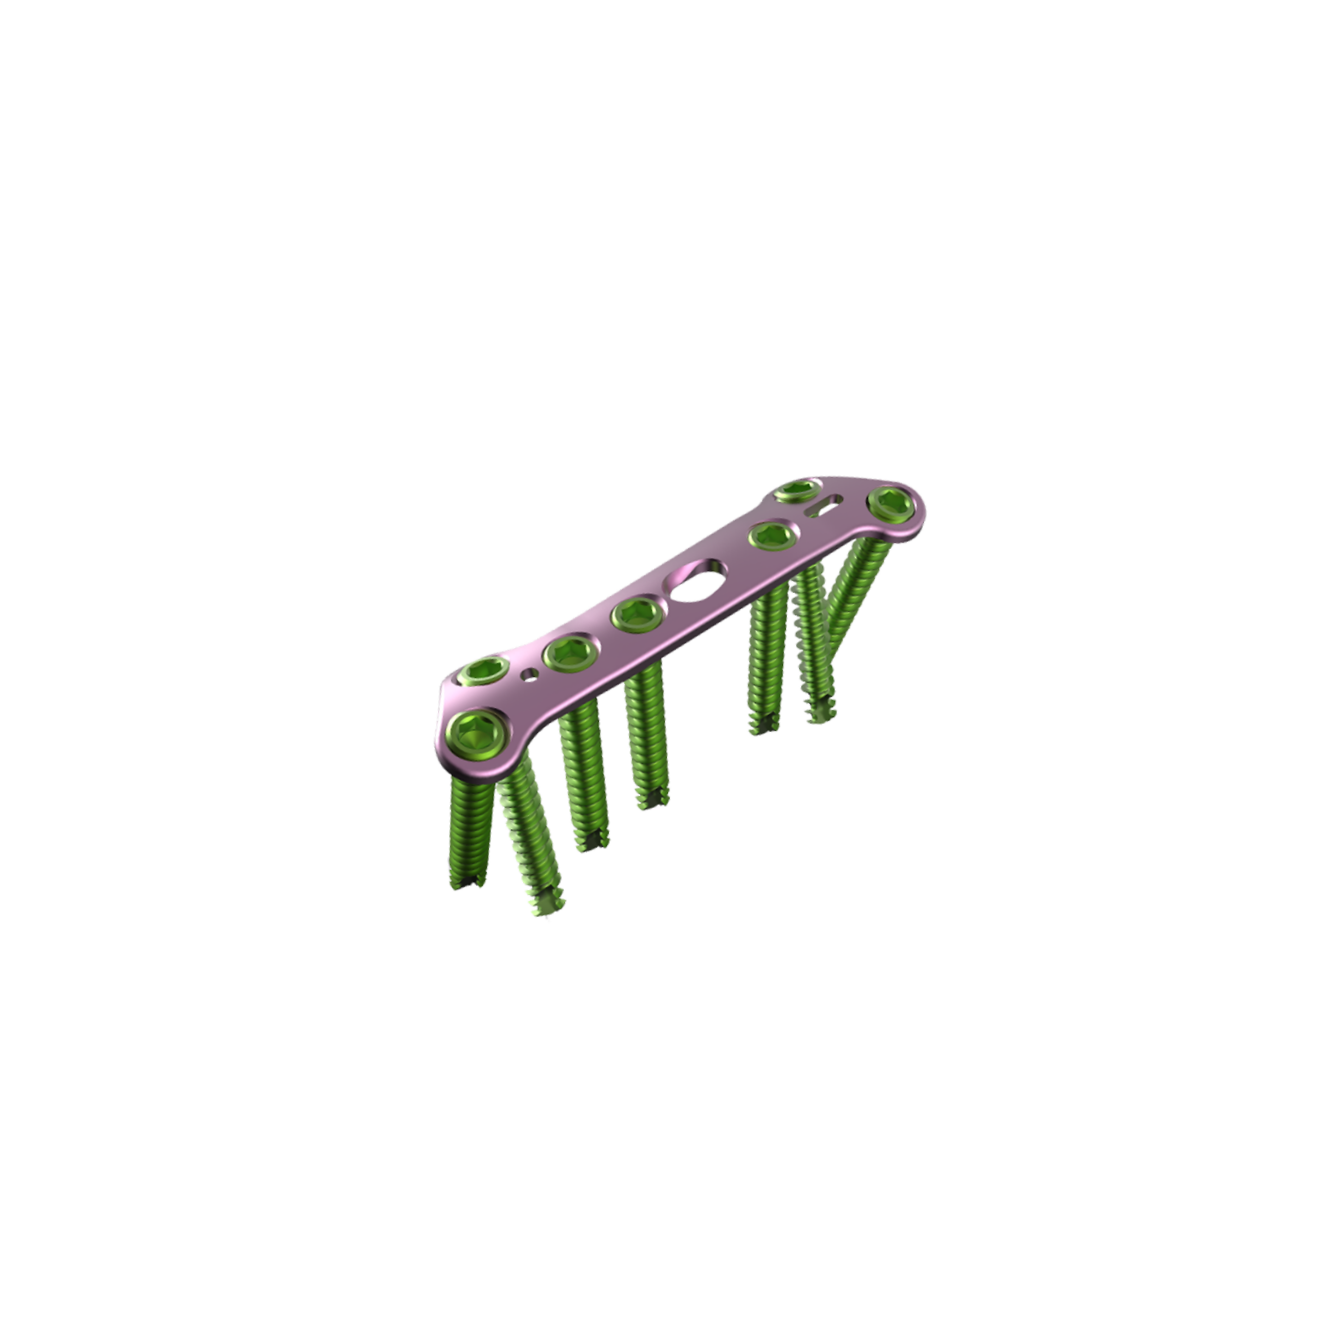

FIRST MTP FUSION PLATE

The First MTP Fusion Plate is an orthopedic implant specifically designed for stabilizing and fusing the first metatarsophalangeal (MTP) joint in cases of arthritis, deformities, or trauma. Made from high-quality Stainless Steel or Titanium, this plate provides strong, stable fixation to facilitate the fusion of the first MTP joint. The low-profile design minimizes soft tissue irritation, ensuring patient comfort during the healing process. Its precise screw placement allows for optimal alignment and fixation of the joint, promoting effective fusion and long-term joint stability.

+ Key Features

- MTP Joint Fusion : Specifically designed to stabilize and support the fusion of the first MTP joint, aiding in effective bone healing.

- Locking and Non-Locking Screw Options : Accommodates both locking and cortical screws, allowing for flexibility in fixation according to patient needs.

- Low-Profile Design : Reduces soft tissue irritation, ensuring a smoother recovery process and minimal post-operative discomfort.

- Made from Stainless Steel or Titanium : Offers superior strength, biocompatibility, and corrosion resistance, ensuring durability over time.

- Anatomically Contoured : Designed to match the natural curvature of the first MTP joint for optimal fit and stability.

- Corrosion-Resistant Finish : Provides long-lasting durability and maintains the implant’s effectiveness throughout the healing process.